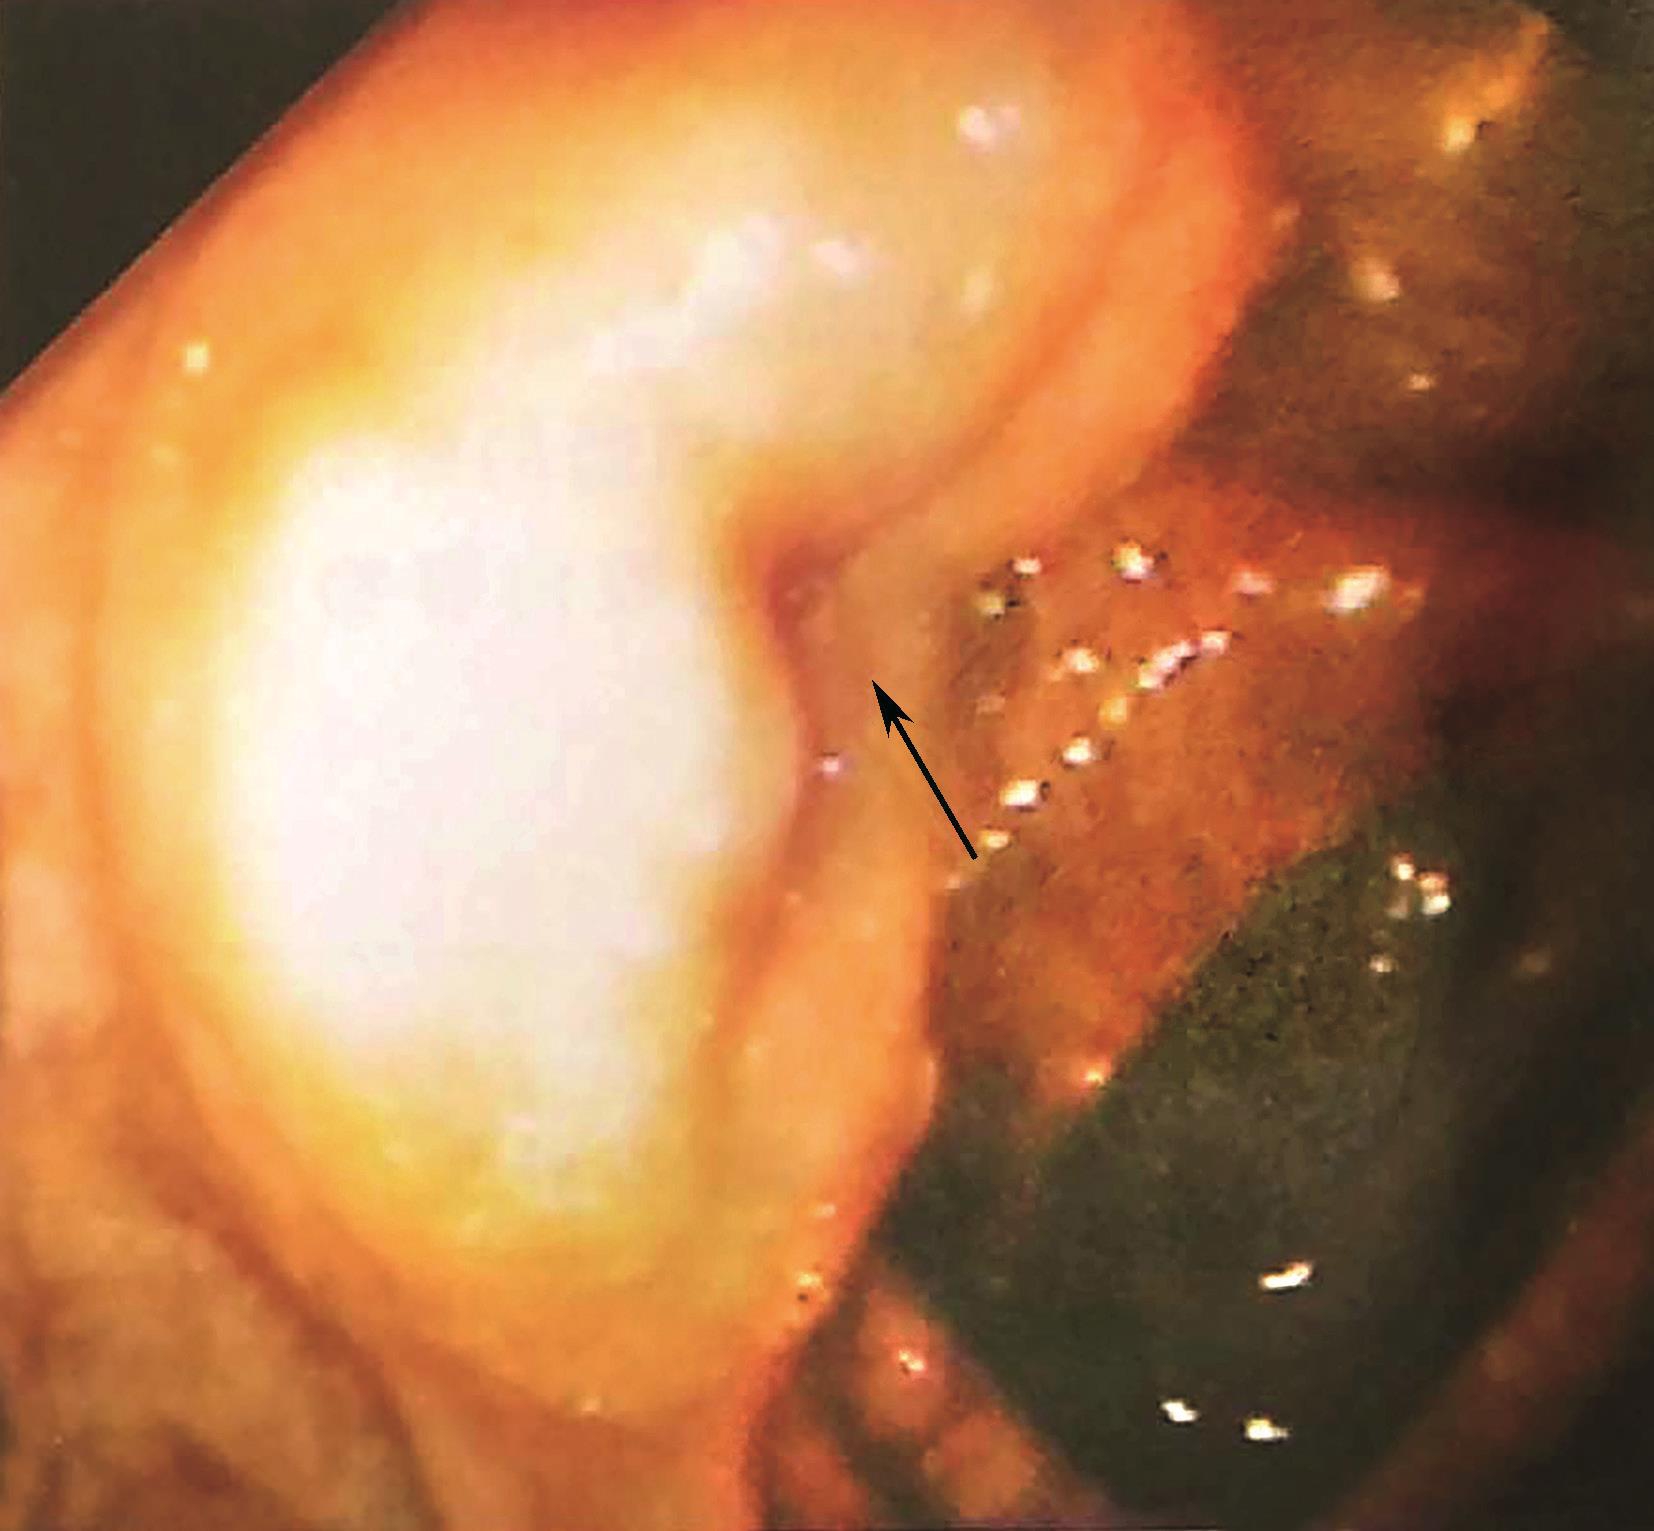

盲肠为腹膜内位器官,移动性较好,没有系膜结构,腹膜折叠常将盲肠附着在髂窝外侧和内侧。这些褶皱形成一个小的陷凹,称为结肠后窝(图2-1)。回肠和盲肠的韧带维持末端回肠和盲肠之间的夹角,形成了回肠末端突入盲肠的类似上下唇样的结构,称回盲瓣(图2-2)。这些结构在调节小肠内容物进入结肠的速度和预防回肠末端的食糜回流发挥重要作用[结肠内压可达80mmHg(1mmHg=0.133kPa)]。因此,临床上不要轻易切除回盲部;在短肠综合征的病例中,是否具有回盲瓣,对该病的诊断和预后均有重要意义。

图2-2 回盲瓣(结肠镜下观)

箭头示回盲瓣。